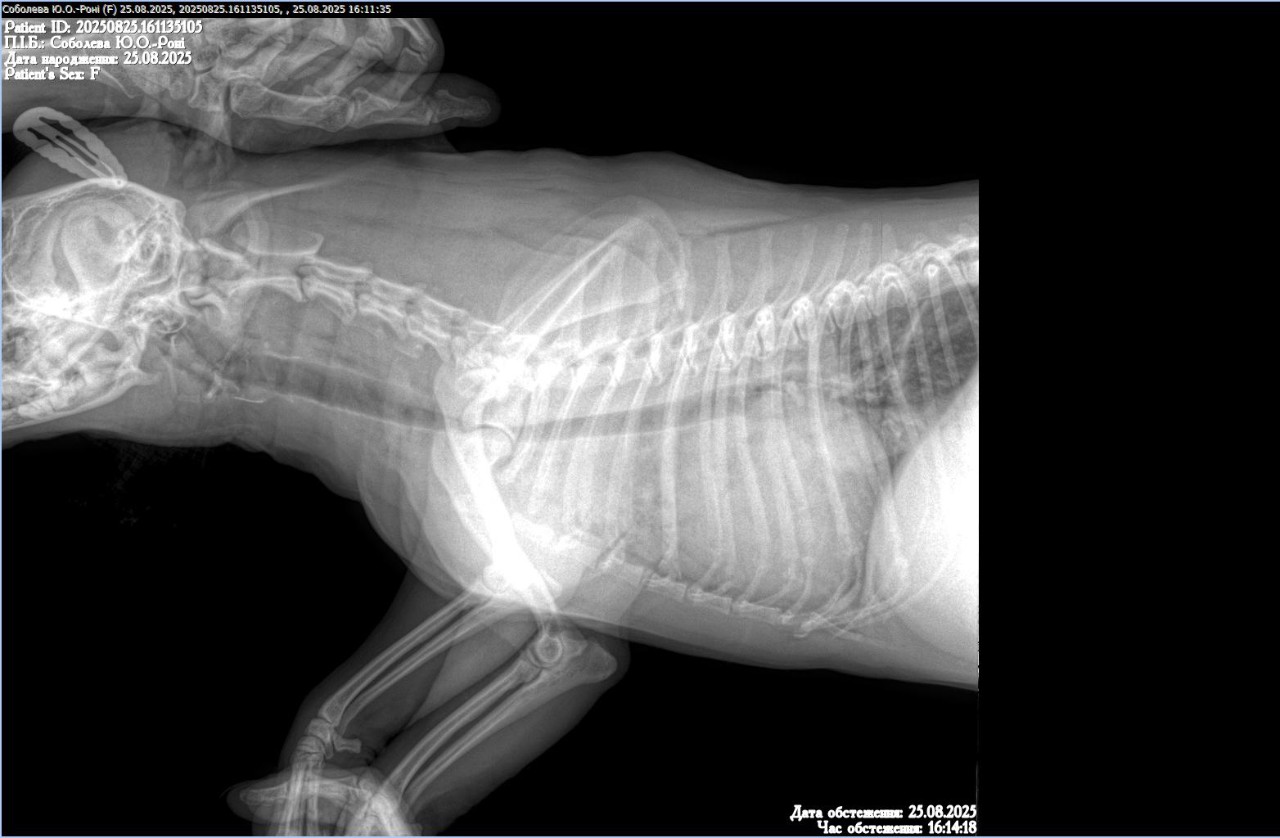

Добрый день уа. Врачи у меня неординая просьба к вам, так как мы находимся прифронтовой зоне и сейчас нет возможности выехать мы не можем помочь своему четверолапому. У него кашель, сердце исключили, сказали искать проблему в легких, рентген нам получилось сделать, а вот описание ренгена нет, ветгруппы нам не помогли. Если это возможно, помогите нам пожалуйста! Очень просим помощи, спасибо.